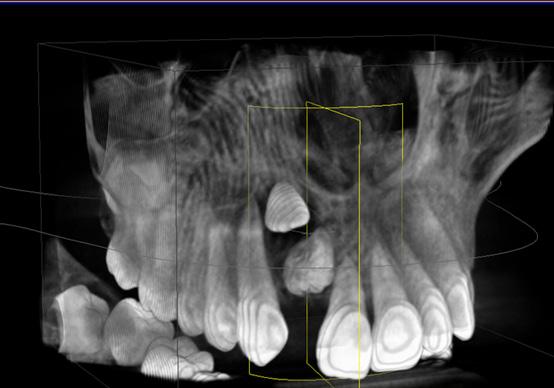

ABSTRACT

Systemic Lupus Erythematosus (SLE) is an autoimmune disease in which organs, tissues and cells are damaged by the exaggerated response of T cells and B cells, loss of immune tolerance against non-specific antigens of the organism. Lupus Enteritis (LE) is defined as vasculitis or inflammation of the small intestine that is diagnosed with the support of imaging and/or biopsy findings. Intestinal pneumatosis (PI) is a rare disease characterized by the presence of intramural gas in the gastrointestinal tract, associated with various clinical conditions, such as pulmonary diseases, gastrointestinal diseases and traumatic injuries, as well as autoimmune disorders.

A bibliographic search was carried out in databases such as PubMed, Nature, Elsevier and Google Scholar, with keywords such as “intestinal pneumatosis” and “lupus enteritis”.

Case presentation: Female patient with a history of surgery for intestinal obstruction, then returned due to a clinical picture of more or less 6 days, in poor general condition with hypotension 80/50 mmHg that did not improve with the administration of crystalloids, for which admission to the Intensive Care Unit (ICU) is indicated, with the need for vasopressors, interconsultation with surgery is carried out where it is decided to perform an exploratory laparoscopy, ruling out intestinal vascular compromise, after starting corticosteroids, the patient shows improvement and is discharged to the general ward in good condition and later home discharge.

Conclusion: Intestinal pneumatosis due to lupus enteritis is one of the rare manifestations with non-specific symptoms where prompt diagnosis and treatment is required. Giving a good response to corticosteroids and avoiding unnecessary surgical interventions.

Key words: Intestinal pneumatosis, lupus erythematosus, lupus enteritis,

INTRODUCCIÓN

El Lupus Eritematoso Sistémico (LES) es una enfermedad autoinmunitaria en la cual los órganos, tejidos y células se dañan por la respuesta exagerada de las células T y células B, perdida de la tolerancia inmune contra antígenos no específicos del organismo (1). La producción y eliminación defectuosa de anticuerpos, también depósitos de complejos autoinmunes, complemento y activación de citocinas (1), permiten el debut con las manifestaciones clínicas con la presencia de un 95 % de compromiso musculo esquelético, un 80 % cutáneas y con menos frecuencia las digestivas, 40 % (3), siendo así que la última que se menciona no forma parte del criterio diagnóstico

por la infrecuencia de los síntomas; la afectación gastrointestinal es una queja común que se observa en el 40 a 60 % de los pacientes con LES; se han descrito manifestaciones gastrointestinales clínicamente reconocidas en el 8 al 10% de los pacientes; por otro lado, los estudios de autopsia, informan hallazgos de compromiso gastrointestinal en el 60 a 70 % de los pacientes lo que sugiere un compromiso subclínico o no reconocido (11).

La Enteritis Lúpica (EL) es definida como una vasculitis o inflamación del intestino delgado con apoyo de hallazgos de imagen y/o biopsia; en la cual la tomografía es el examen de elección que nos muestra una mayor visibilidad de los vasos